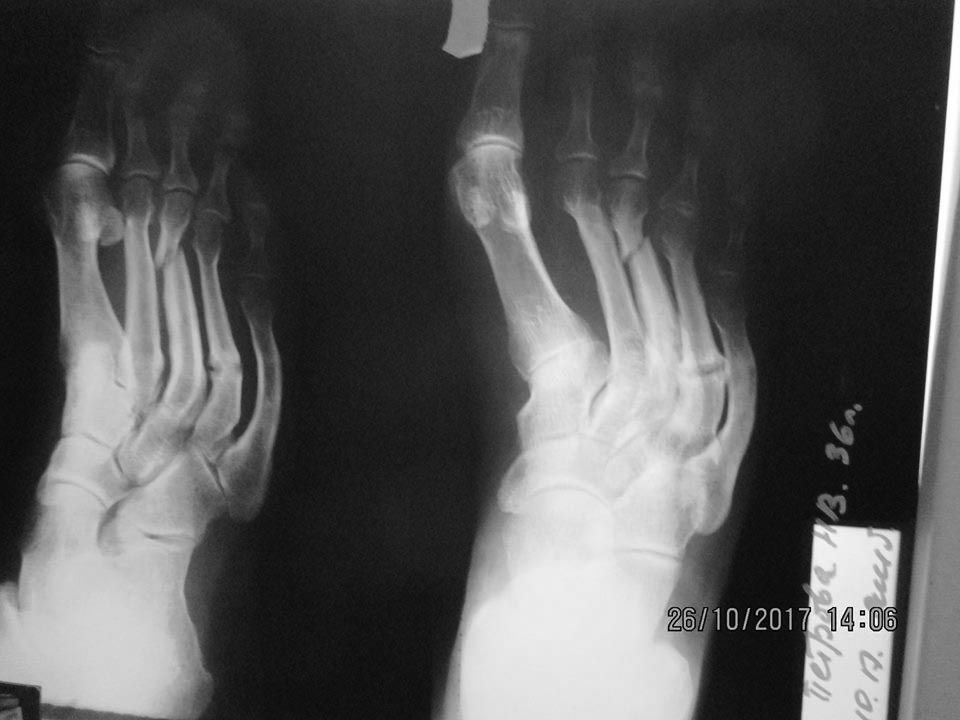

Пациентка 36 лет, несколько избыточного веса. За неделю до обращения почувствовала боль в правой стопе. В 2015 была аналогичная ситуация, тогда болевой синдром продолжался в течение 3-х месяцев. Местно: на тыльной поверхности переднего отдела - отёк, гиперемия и боль при пальпации; форма стоп – обычная. На рентгенограмме: перелом дистальной трети III-ей плюсневой кости со смещением, консолидированный перелом проксимальной трети IV-ой (V-ой?) плюсневой кости, дугообразная деформация III-V-ых плюсневых костей. От госпитализации отказалась. Наложена гипсовая лонгета, рекомендовано обратиться к эндокринологу (остеопороз?). Через 1,5 мес. – сращение перелома (рентгенография левой стопы – без особенностей). Лабораторное исследование у эндокринолога пока не выявило какой-либо патологии (УЗИ щитовидной и паращитовидных желез – 15.01.18).Три «незаметных» перелома! Что Вы думаете, господа, по этому поводу?

Интересная рентгенологическая картина! Стрессовые переломы различной давности... И все с одной стороны.